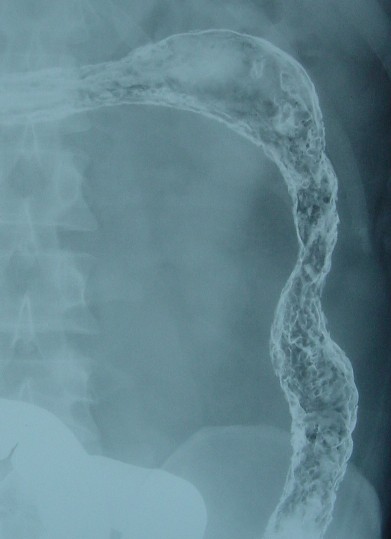

レミ前(2002年10月21日)